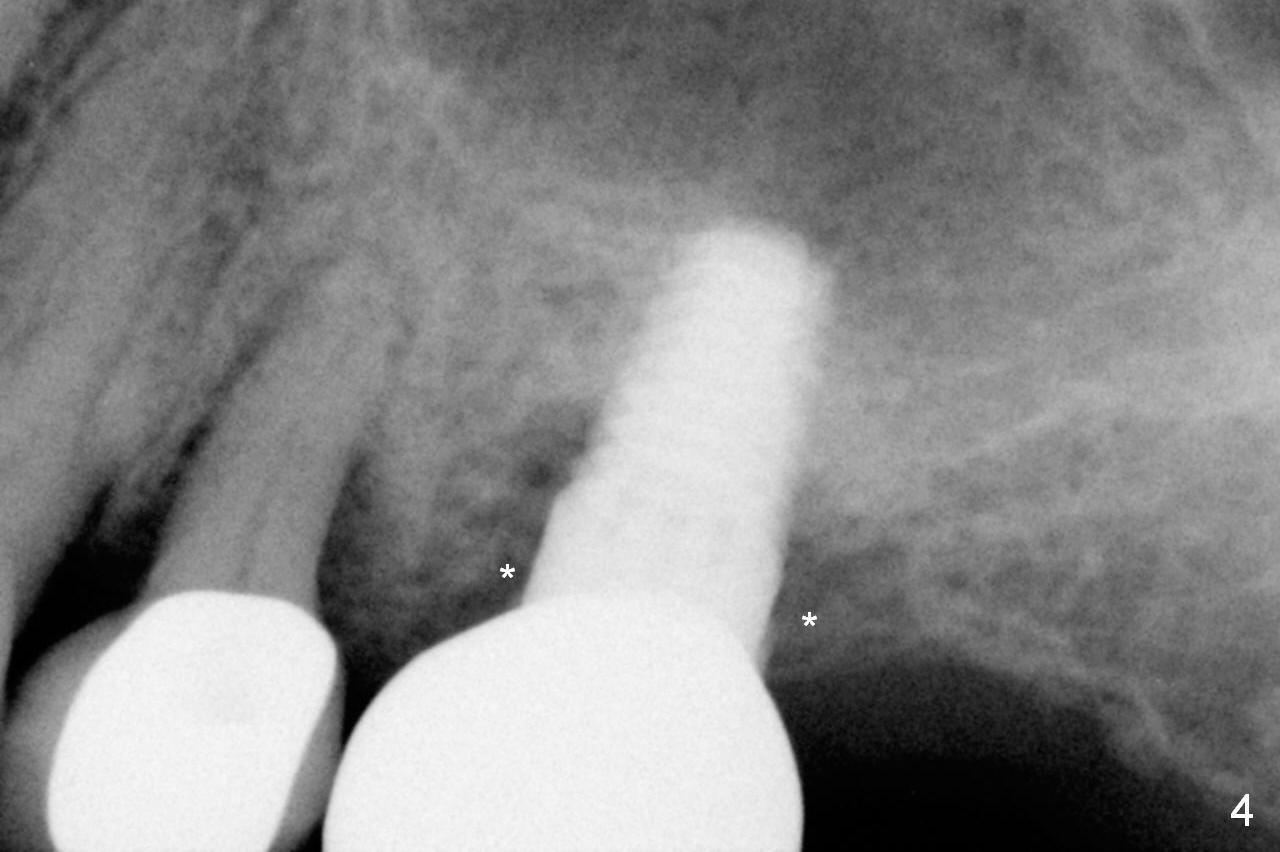

A 73-year-old woman is a possible bruxer with partial edentulism; the tooth #13 had increased periodontal ligament (pdl) space 4 years ago (Fig.1 *). A 5x14 mm tissue-level implant is placed at the site of #14 (Fig.2). The implant appears to be osteointegrated in 6 months (Fig.3). There is crestal bone loss 8 months post cementation (Fig.4 *). The persistent increased pdl at #13 is most likely associated with occlusal tramua from the tooth #19 (Fig.5 (13 months post cementation of #14)). Three years post #14 cementation, the tooth #13 has mobililty II (Fig.6); bone density increases around the apical half of the implant (arrowheads). Normally bone density is the highest coronally where functionality dictates. This indicates the bone loss is getting worse at #14 as well.